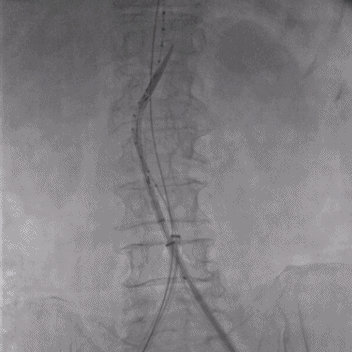

面对这一临床难题,瑞金医院心脏外科团队决定启用最新的EXCC可主动调控腹主动脉覆膜支架系统。手术在赵强副院长的指导下,由王哲主任医师团队实施。术中,团队通过股动脉微创入路,将支架系统送至病变部位。最关键的一步,是利用调节导丝对支架近端进行角度微调,使其完美顺应85度锐角瘤颈。随着支架分段释放,造影显示:动脉瘤被完全隔绝,近端实现零内漏贴附,血流恢复正常,支架与血管壁严丝合缝!手术顺利完成。

支架通过导丝主动调弯瞬间

支架植入前、后对比